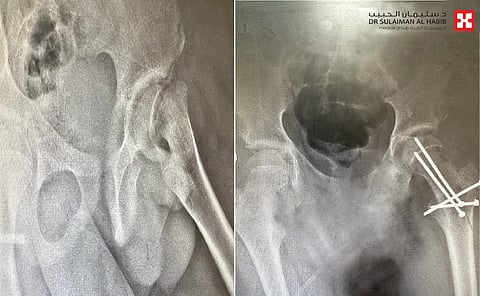

وقال د.الرفاعي أن الطفل الذي يبلغ من العمر "11" عاماً، أحضر إلى الطوارئ محمولاً على "سرير متحرك" لعدم قدرته على المشي على قدميه، إضافة إلى أنه كان يعاني من آلام تزداد حدتها مع الحركة بمفصل الورك والفخذ، منذ ما يزيد عن "6" أشهر، وزار خلال تلك الفترة العديد من المستشفيات والمراكز إلا أن العلاج الذي تلقاه لم يحسن حالته الصحية، فراجع مستشفى الدكتور سليمان الحبيب، وفور وصوله إلى الطوارئ خضع لحزمة من الفحوصات الطبية الدقيقة، أبرزها التصوير بالأشعة السينية والرنين المغناطيسي، وأظهرت النتائج وجود انزلاق وانفصال في نهاية عظم الفخذ عند صفيحة النمو في مفصل الورك، تم ادخال المريض لغرفة العمليات بصوره مستعجلة وخضع لعملية خلع ورك جراحي آمن، وارجاع صفيحة رأس الفخذ إلى وضعه الطبيعي، وعزل حزمة الأوردة والشرايين المغذية لرأس الفخذ وتثبيتها في مكانها الطبيعي، باستخدام تقنية Modified Dunn Procedure، كما تم التأكد من استمرارية تدفق الدم إلى رأس الفخذ.

وأضاف د. الرفاعي أن العملية مضت وفقاً للخطة العلاجية، وانتهت ولله الحمد بالنجاح التام، ونُقل الطفل من غرفة العمليات مباشرة إلى غرفة التنويم حيث أمضى منوماً قيد العناية الطبية الحثيثة لمدة "5" أيام، قبل أن يغادر المستشفى بحالة صحية جيدة، بعدما تخلص من الآلام، وبعد نحو "8" أسابيع ومع العلاج الطبيعي استعاد قدرته على الحركة، والآن وبعد مرور "4" أشهر من العملية أصبح يمارس الرياضة بصورة طبيعية.